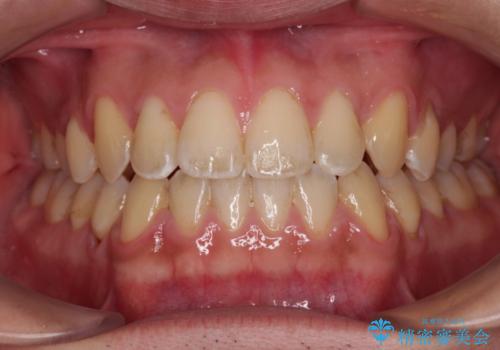

インビザラインによる矯正治療(非抜歯) 前歯の突出と上下の歯並びのガタつきの改善